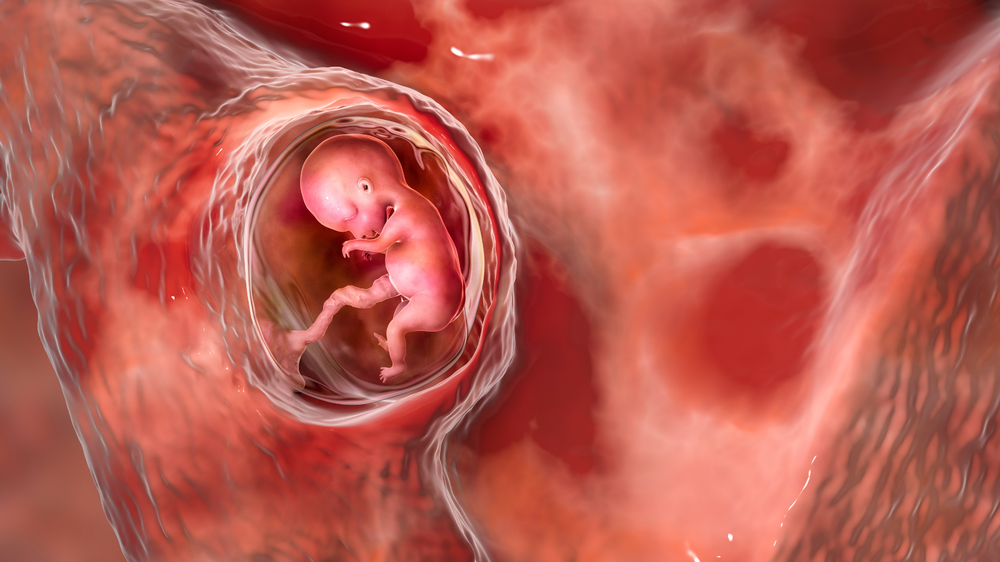

Why Babies Grow in Spurts Instead of a Straight Line Inside the WombOnce you get pregnant, your baby’s growth doesn’t always happen in a consistent manner. Rather, they grow in spurts, periods of rapid development followed by slower phases. This is a usual pattern and crucial for healthy development. Knowing why babies follow such a growth pattern during pregnancy can make you feel calmer during ultrasounds. It also helps you understand what to expect about your baby’s size and weight. It can also assist you in taking better care of yourself, both physically and emotionally.